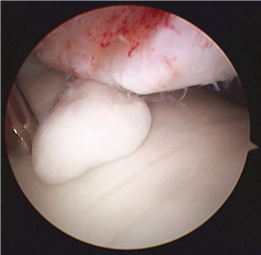

Clinical & Radiographic Imaging Archive

Clinical Image